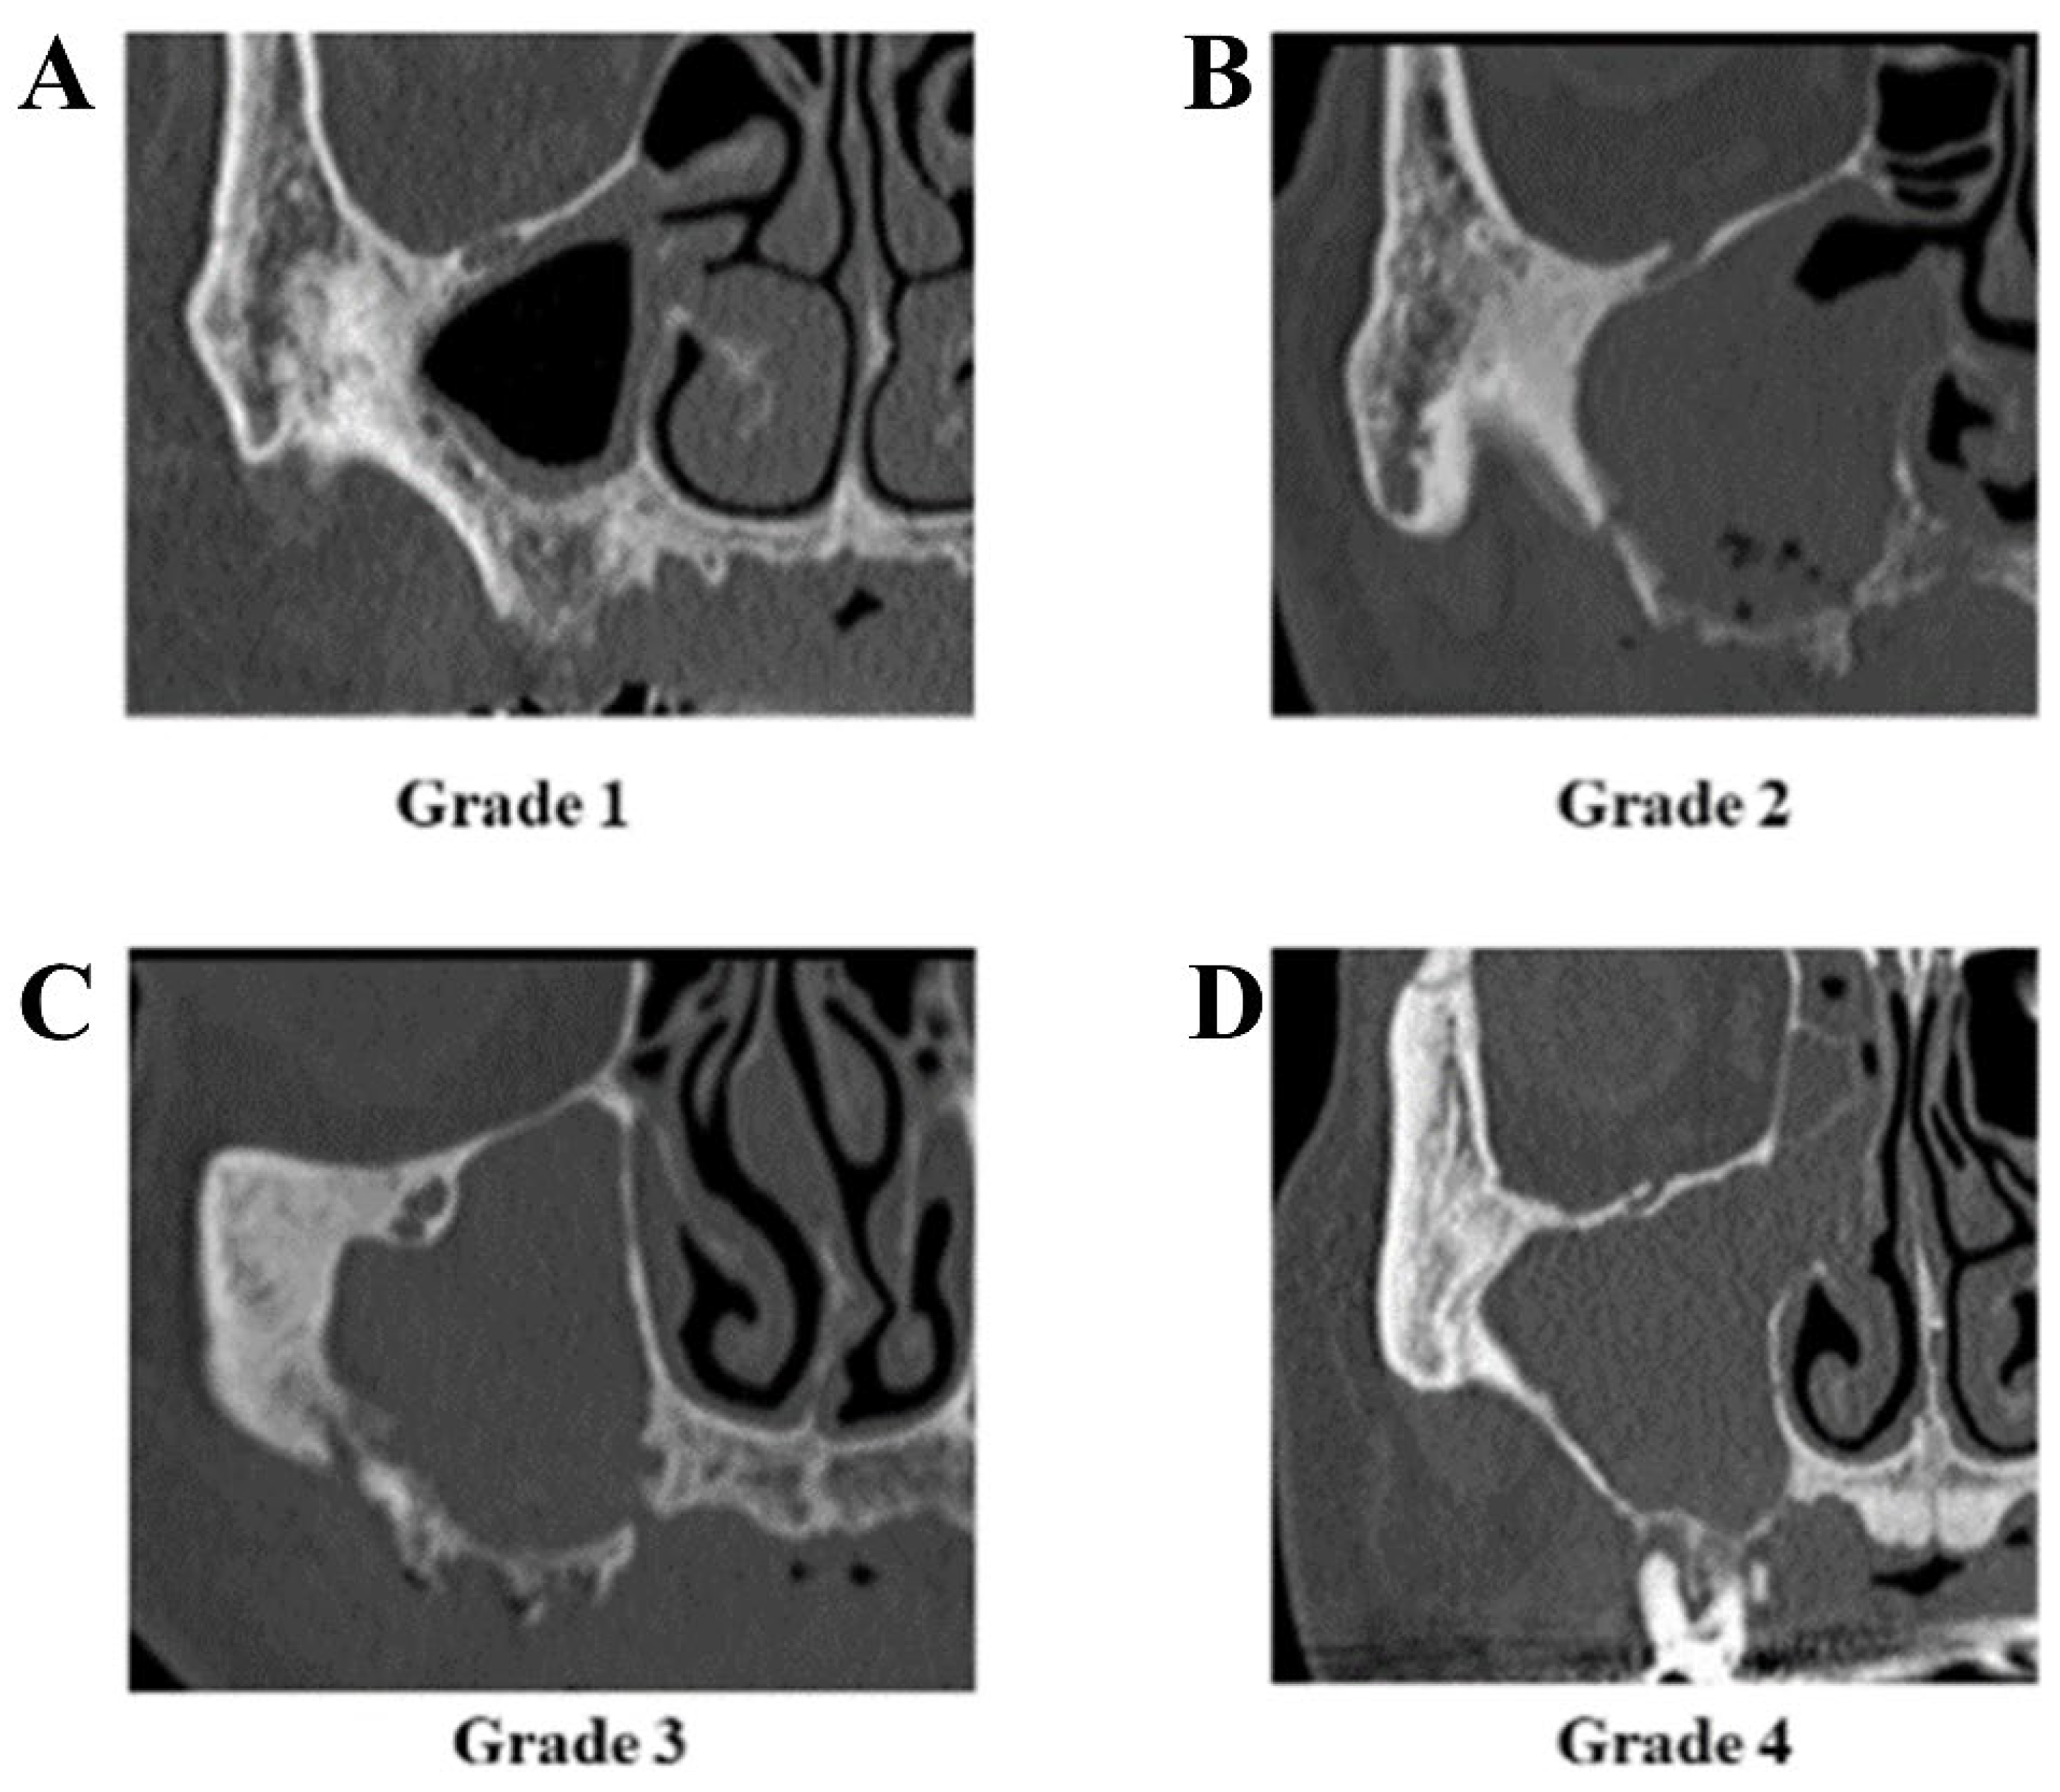

| Grade of sinusitis | grade 1 | 7 |

| grade 2 | 9 | |

| grade 3 | 1 | |

| grade 4 | 17 | |